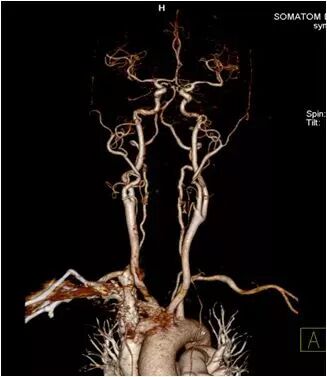

完成全身动脉检查仅需3秒

西门子双源CT(SOMATOM Drive)头颈部联合检查,扫描时间不到3秒,所得图像可清晰诊断颈部动脉及颅内动脉疾病。